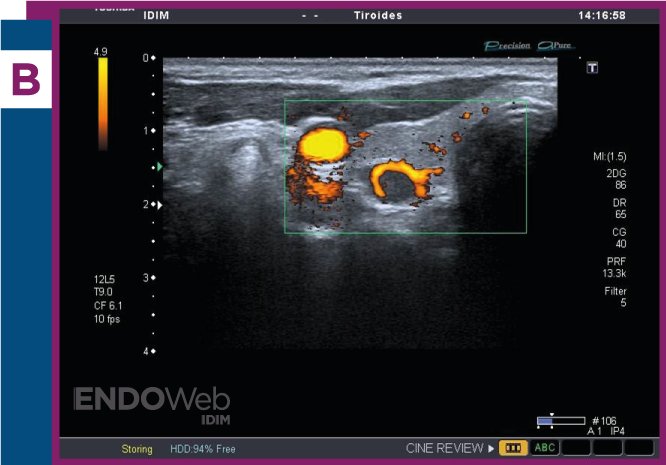

Paciente mujer de 55 años, con diagnóstico de hiperparatidoidismo primario, a quien se le solicita ecografía de cuello, para búsqueda de lesión paratiroidea

Laboratorio: Calcemia 11.2mg/dL, fosfatemia 1.9mg/dL, PTHintacta 128 pg/mL, 25OHvitamina D 33 ng/mL

Ecografía cervical, donde se observa en topografía paratiroidea, nódulo sólido e hipoecoico, con imagen al doppler compatible con signo del arco vascular que rodea nódulo paratiroideo en más de 180° de su contorno y se visualiza en las imágenes al doppler color (A) y doppler power (B).